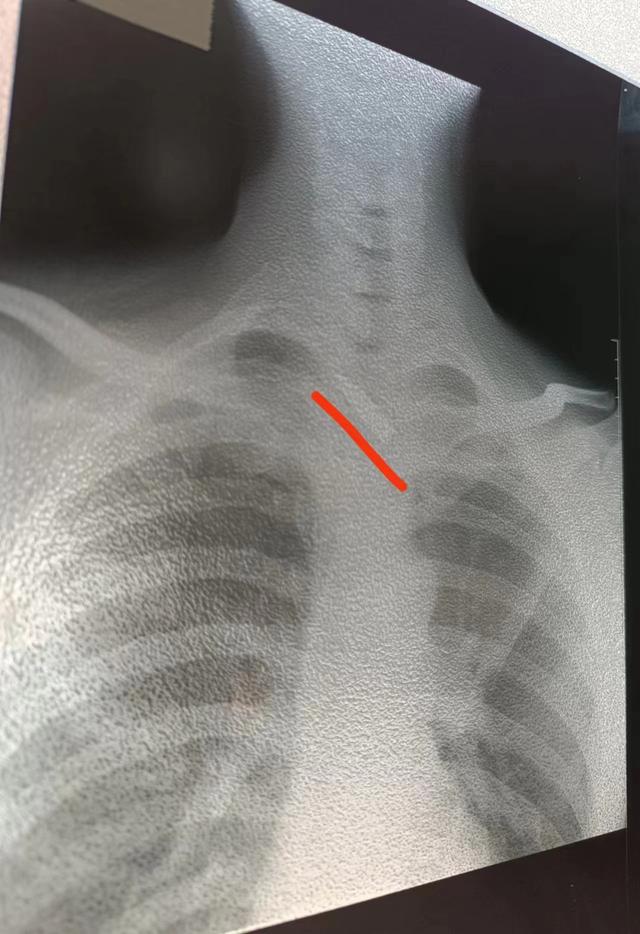

厄特男子颈部中弹10余年,河南省肿瘤医院邢宏彬冒险取出